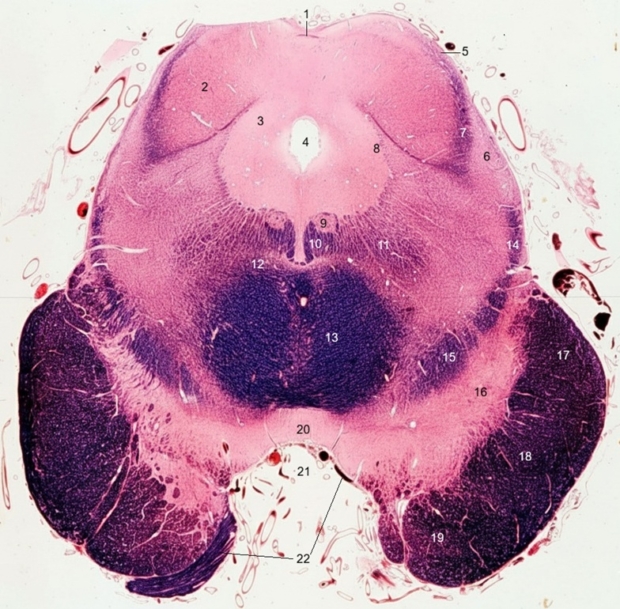

1. Commissure of inferior colliculus

2. Inferior colliculus

3. Periaqueductal gray

4. Cerebral aqueduct

5. Brachium of inferior colliculus

6. Corpus parabigeminum

7. Lateral lemniscus

8. Mesencephalic tract and nucleus of trigeminal nerve

9. Trochlear nucleus

10. Medial longitudinal fasciculus

11. Central tegmental tract